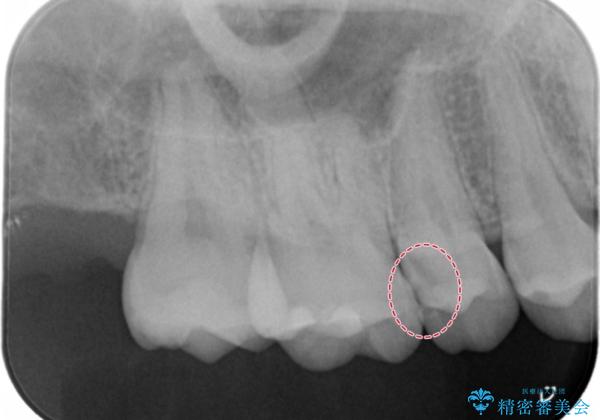

検査の結果、症状はないものの右上の奥歯に虫歯が見つかりました。

局所的に深い虫歯が確認されましたが、神経は温存することができました。

歯と歯の間から広がる虫歯は目視では確認しにくいため、定期的にチェックし悪化を予防することが大事です。